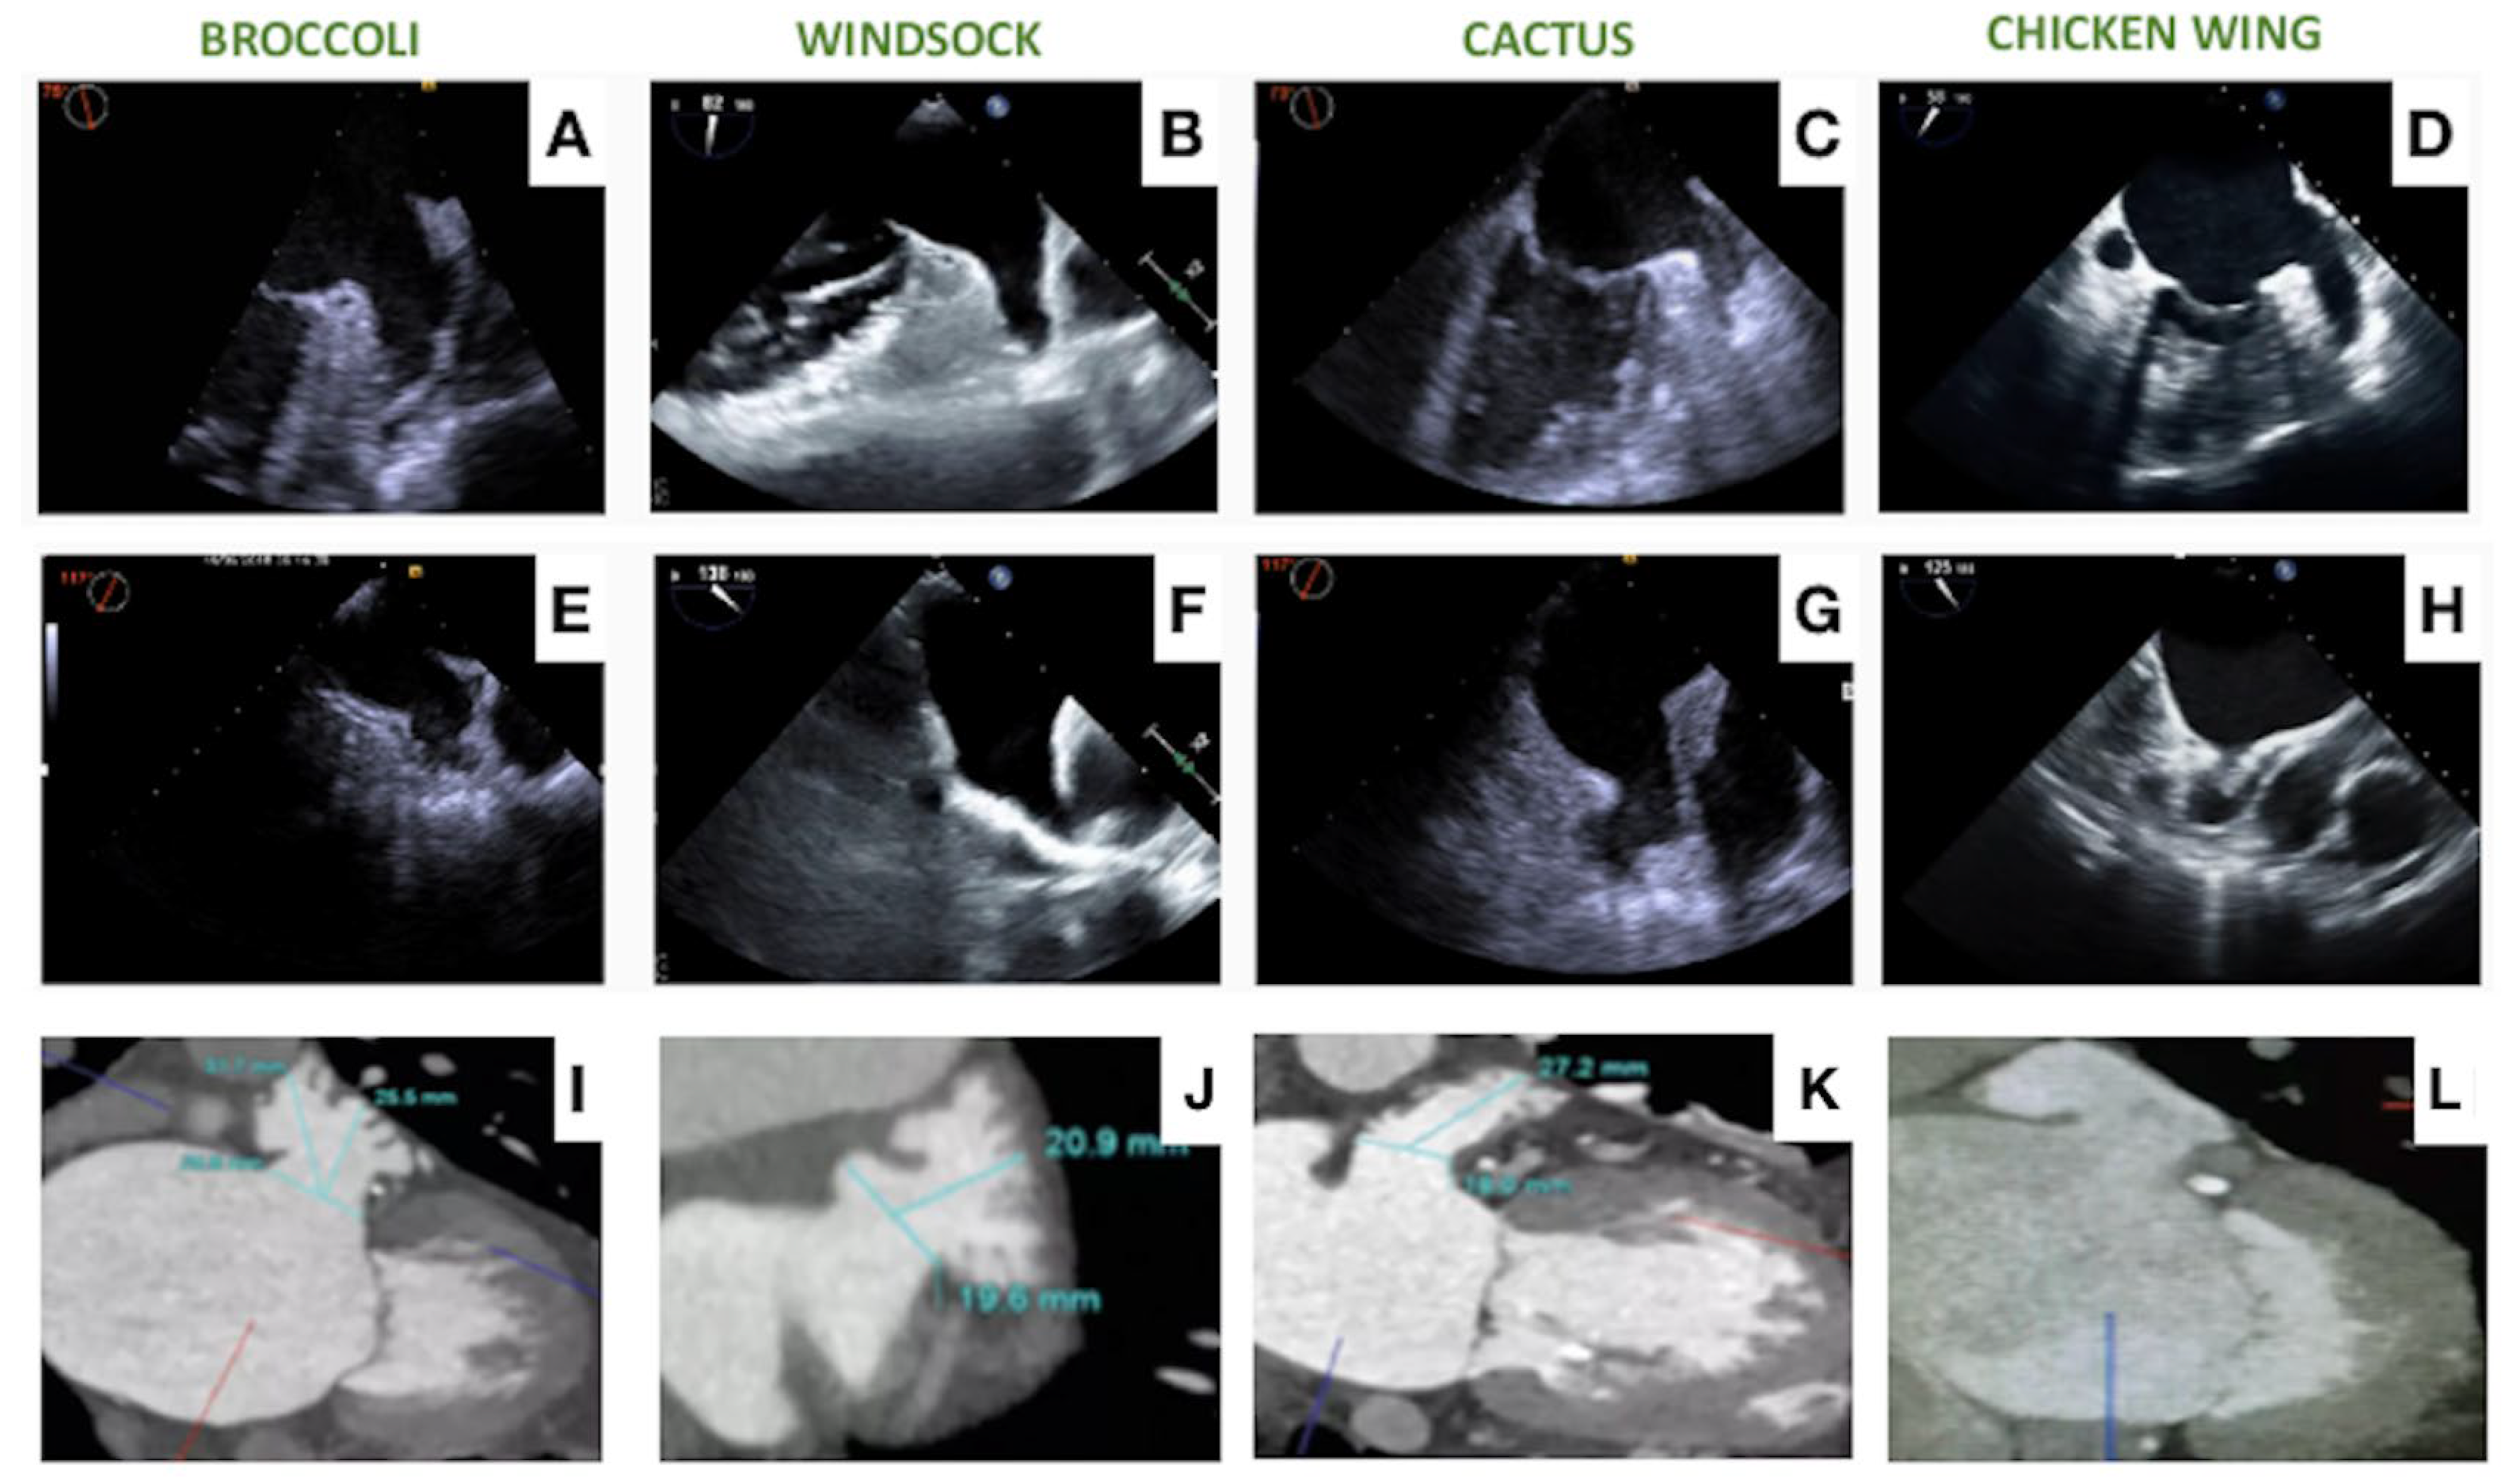

- Clemente, A.; Avogliero, F.; Berti, S.; Paradossi, U.; Jamagidze, G.; Rezzaghi, M.; Della Latta, D.; Chiappino, D. Multimodality imaging in preoperative assessment of left atrial appendage transcatheter occlusion with the Amplatzer Cardiac Plug. Eur. Heart J. Cardiovasc. Imaging 2015, 16, 1276–1287. [Google Scholar] [CrossRef]

- Korsholm, K.; Jensen, J.M.; Nørgaard, B.L.; Samaras, A.; Saw, J.; Berti, S.; Tzikas, A.; Nielsen-Kudsk, J.E. Peridevice Leak Following Amplatzer Left Atrial Appendage Occlusion: Cardiac Computed Tomography Classification and Clinical Outcomes. JACC Cardiovasc. Interv. 2021, 14, 83–93. [Google Scholar] [CrossRef]